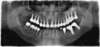

vue avant traitement

pose de 6 implants au niveau des prémolaires et molaires, sous jacent à un comblement osseux sous-sinusien

vue panoramique après traitement des 6 piliers titane et couronnes céramiques définitifs